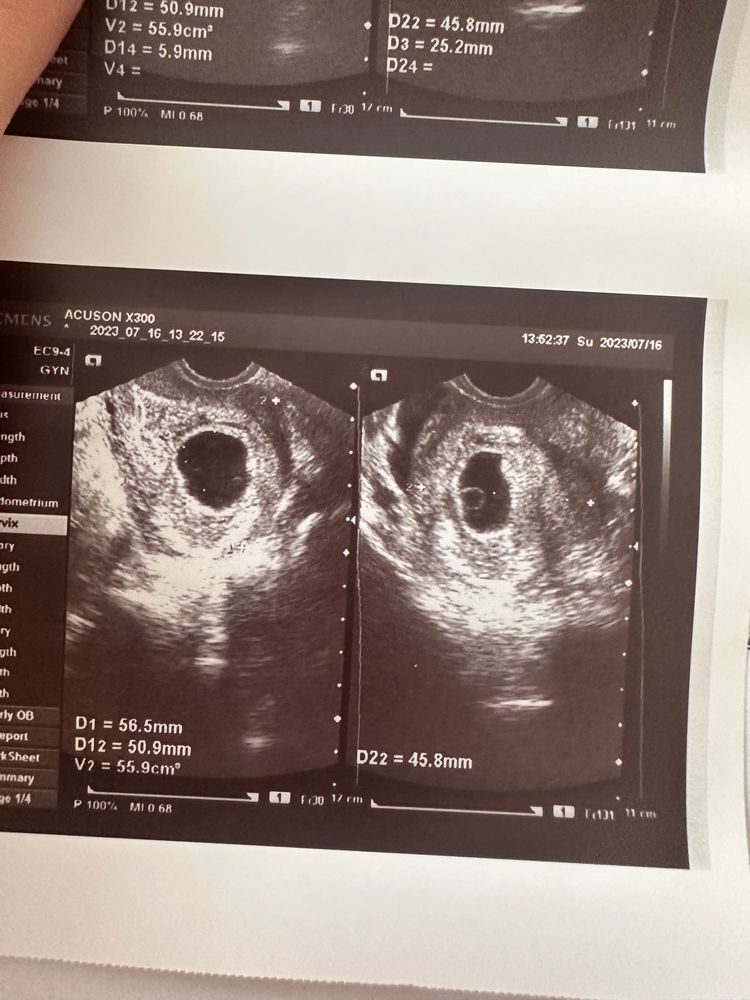

Нету эмбриона 7 недель

Увы с таким размером пя, уже все должно быть.. сходите в другое место, но не затягивайте.. тут ждать уже нечего к сожалению.. только надеяться на плохой аппарат и глаза.. но это при таком размере уже тоже почти исключено 😩 хгч нет смысла сдавать - говорю по своему опыту. У меня рос прекрасно.. до 47 тыс. И у вас наверняка большой, потому что плодное яйцо растет.. оно выделяет хгч.. а еще у вас желточный мешочек большой. Это тоже не хорошо

Анэмбриония это,тоже самое было и пя такого же размера и жм тоже больше нормы и срок тоже 7 недель,увы, ничего не появилось,большой жм при отсутствии эмбриона уже говорит о том,что эмбрион с аномалиями был и замер на этапе формирования и на УЗИ его не видно,только какой смысл вам врач написал хгч в динамике,при анэмбрионии пя растет и хгч тоже,но это не значит что беременность развивается, эмбрион к хгч отношения не имеет

Обязательно сходить на другой аппарат узи, овуляция отслеженная ? Срок не может быть меньше? Конечно из минусов жм великоват и пя от 20 мм должен уже быть виден эмбриончик.. не расстраивайтесь если малыш сильный и здоровый то все покажется 🙏👼🏼🌺

С таким размером пя, очень большой жм- увы это анэмбриония.

Плодное яйцо больше 25 мм без эмбриона это критерий анэмбрионии. Сходить в другое место можно, но тут надежда только на ошибку.

Увы. И Пя уже большое и жм большой, а эмбриона и сб нет.

Пя больше 25 мм и пустое... Увы